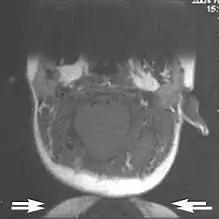

Flow can manifest as either an altered intravascular signal (flow enhancement or flow-related signal loss), or as flow-related artifacts (ghost images or spatial misregistration). Flow enhancement, also known as inflow effect, is caused by fully magnetised protons entering the imaged slice while the stationary protons have not fully regained their magnetization.[1] The fully magnetized protons yield a high signal in comparison with the rest of the surroundings. High velocity flow causes the protons entering the image to be removed from it by the time the 180-degree pulse is administered. The effect is that these protons do not contribute to the echo and are registered as a signal void or flow-related signal loss (Fig. 2).[1] Spatial misregistration manifests as displacement of an intravascular signal owing to position encoding of a voxel in the phase direction preceding frequency encoding by time TE/2.The intensity of the artifact is dependent on the signal intensity from the vessel, and is less apparent with increased TE.[1]